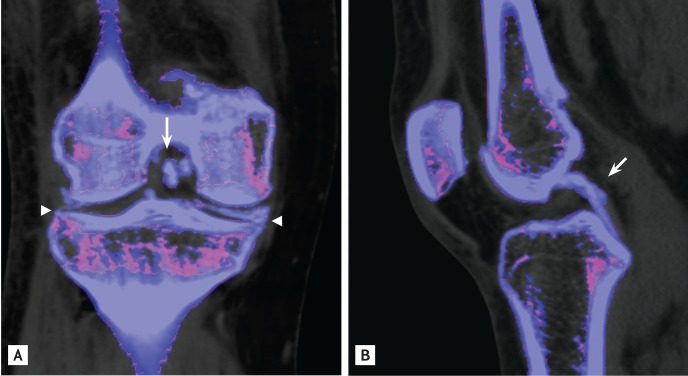

A 52-year-old woman presented with painful swelling in both knees for 7 days. Physical examination identified marked swelling and tenderness in both knee joints that she reported to have recurred for the past 6 years. Laboratory tests determined the erythrocyte sedimentation rate to be 107 mm/hr, C-reactive protein as 25.55 mg/dL, and serum uric acid levels as 4.1 mg/dL. Calcium pyrophosphate dihydrate (CPPD) crystals were found on polarized light microscopy examination of knee joint synovial fluid. Cultures identified no microorganisms. Plain radiography of the right knee revealed multiple calcifications in the medial and lateral menisci and the femoral condylar cartilage (Fig. 1). Dual-energy computed tomography (DECT), which differentiates monosodium urate (color-coded in green) from calcium (color-coded in blue), revealed multiple calcium depositions in the anterior and posterior cruciate ligaments, as well as in both menisci and the femoral condylar cartilage (Fig. 2). The patient was diagnosed as having CPPD crystal deposition disease of both knee joints. Intra-articular injection of triamcinolone effectively relieved her pain.